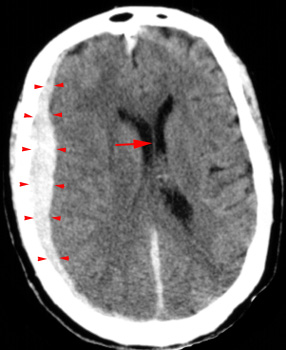

Head CT > Trauma > Acute Subdural Hematoma

Acute Subdural Hematoma

Deceleration

and acceleration or rotational forces that tear bridging veins can cause

an acute subdural hematoma. The blood collects in the space between the

arachnoid matter and the dura matter. The hematoma on CT has the following

characteristics:

- Crescent shaped

- Hyperdense, may contain hypodense foci due to serum, CSF or active bleeding

- Does not cross dural reflections